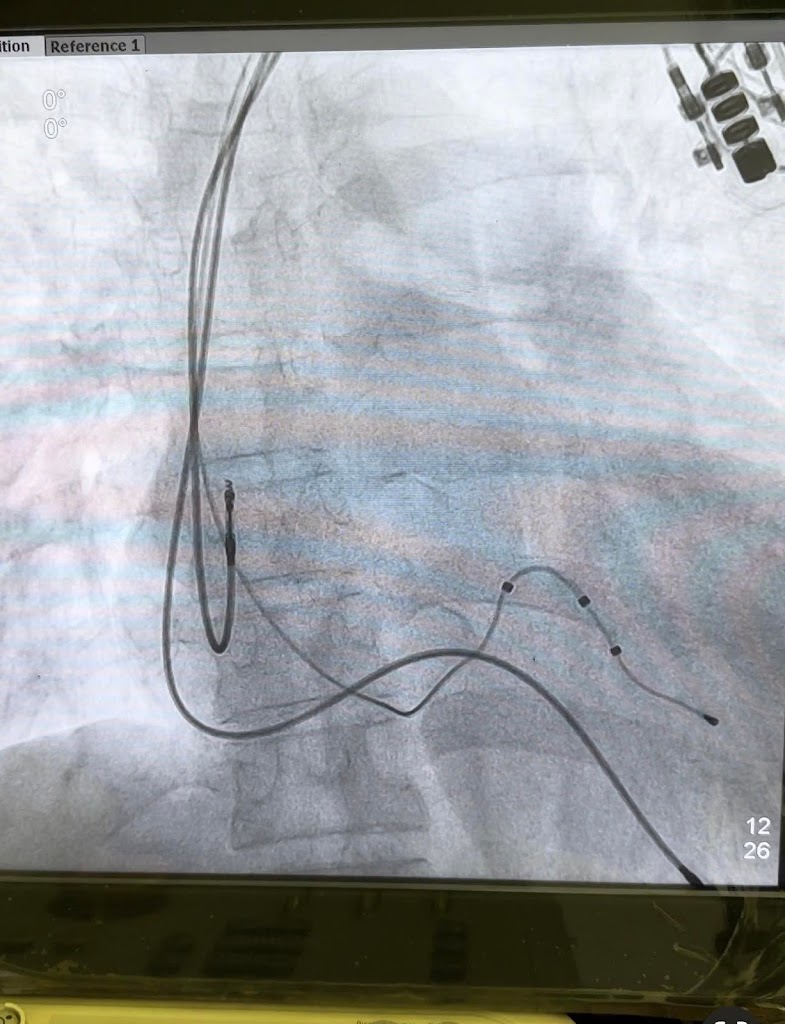

Dr. Chatterjee's diagnostic capabilities are clearly at the forefront, particularly with the availability of Echocardiography. This vital service is performed with meticulous attention, providing precise insights into the heart's structure and function. For those requiring more invasive diagnostic or interventional procedures, the provision of Angiography underscores the chamber's commitment to complete cardiac care.